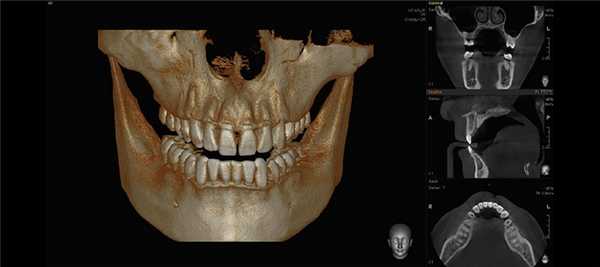

В первое посещение под инфильтрационной анестезией при изоляции коффердама были снята реставрация с 4.7 зуба, распломбированы дистальные каналы, получен гнойный экссудат. После снятия острой боли пациентка была направлена на КЛКТ.

На томограммах и реконструктивных снимках было установлено, что 4.6, 4.7 зубы имеют особенность микроанатомии каналов. Мезиальные корни содержали по 2 канала, которые открывались отдельными апикальными отверстиями. В дистальных корнях обнаружили по 3 канала, которые сливались в одно апикальное отверстие. Причем третий (дистально-язычный) канал 4.7 зуба заканчивался на язычной стенке корня на уровне его середины (рис. 2) .

Рис. 2. КЛКТ. Аксиальные последовательные срезы 4.6, 4.7 зубов.

Качество пломбирования 4.7 зуба, по данным КЛКТ, было неудовлетворительным. В мезиально-щечном и дистальных каналах 4.7 зуба пломбировочный материал прослеживался в виде отдельных фрагментов (рис. 3) . Мезиально-язычный канал обтурирован неплотно, до апикальной стриктуры (рис. 4). Наблюдали признаки апикальной резорбции дистального корня (рис. 5) .

Рис. 3. КЛКТ, косо-сагиттальная и корональная томограммы мезиального корня 4.7 зуба. Выведен мезиально-щечный канал 4.7 зуба.

Рис. 4. КЛКТ, косо-сагиттальная и корональная томограммы мезиального корня 4.7 зуба. Выведен мезиально-язычный канал 4.7 зуба.

Рис. 5. КЛКТ, косо-сагиттальная и корональная томограммы дистального корня 4.7 зуба.

В периапикальной области обоих корней определялся обширный сливной очаг деструкции кости протяженностью 11х6 мм, который распространялся до кортикальной выстилки нижней челюсти канала с ее локальным разрушением (рис. 6) .

Рис. 6. КЛКТ, МПР. Прицельная визуализация апикальных очагов деструкции в обл. 4.7 зуба.